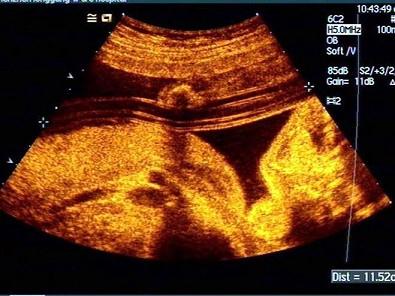

胎儿超声检查如图,图中管道样结构是?(?)A.脊柱B.羊膜囊C.脐带血管平行征D.淋巴管囊肿E.四肢

问题 胎儿超声检查如图,图中管道样结构是?(?)

选项 A.脊柱 B.羊膜囊 C.脐带血管平行征 D.淋巴管囊肿 E.四肢

答案 C